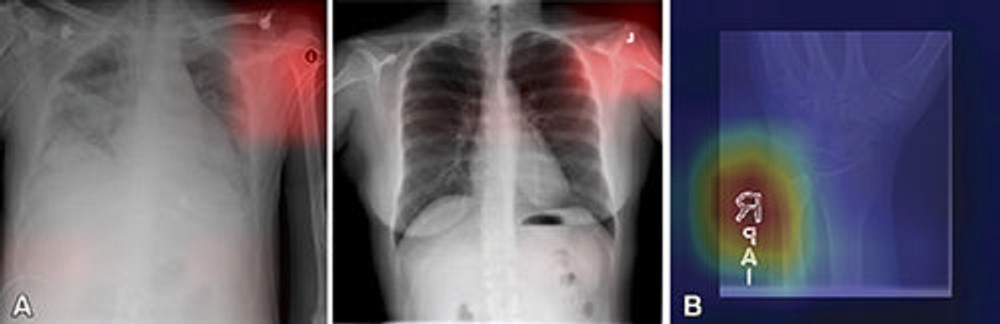

Figure 3. (A) Images from a deep learning (DL) model in radiology that can learn to identify confounding features related to bias and unfair predictions, including laterality markers (image annotations indicate the side of the body being viewed [right vs left]) to identify the hospital at which a chest X-ray was obtained. Images adapted and reprinted from Zech, et al. “Variable Generalization Performance of a Deep Learning Model to Detect Pneumonia in Chest Radiographs: A Cross-sectional Study,” an open-source article, published under the Creative Commons license (CC BY 4.0). (B) Image from a DL model that can make a diagnosis of radiographic abnormality on extremity radiographs, also known as shortcut learning. Reprinted, with permission, from Yi, et al. “Deep Learning Algorithms for Interpretation of Upper Extremity Radiographs: Laterality and Technologist Initial Labels as Confounding Factors.”